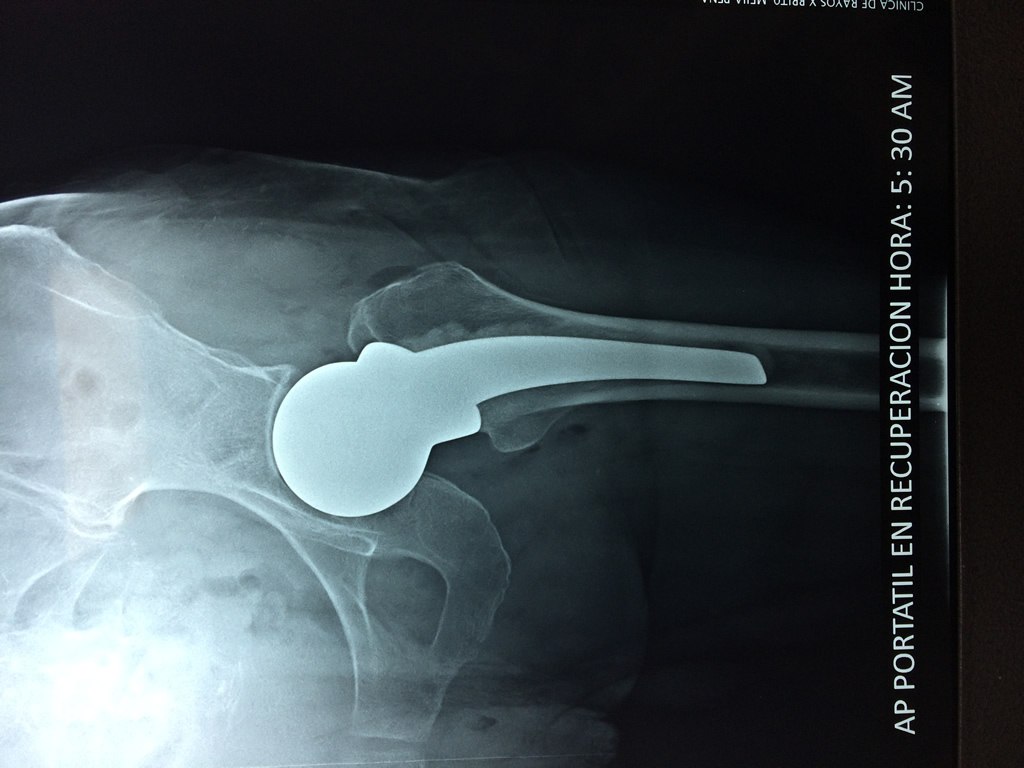

Cirugías de Húmero - Cadera

La cirugía de fractura de cadera se realiza para reparar una ruptura en la parte superior del hueso del muslo. Este hueso se denomina fémur.

Es parte de la articulación coxofemoral. Si una fractura de cadera no recibe tratamiento, es posible que deba permanecer en una silla o en la cama.